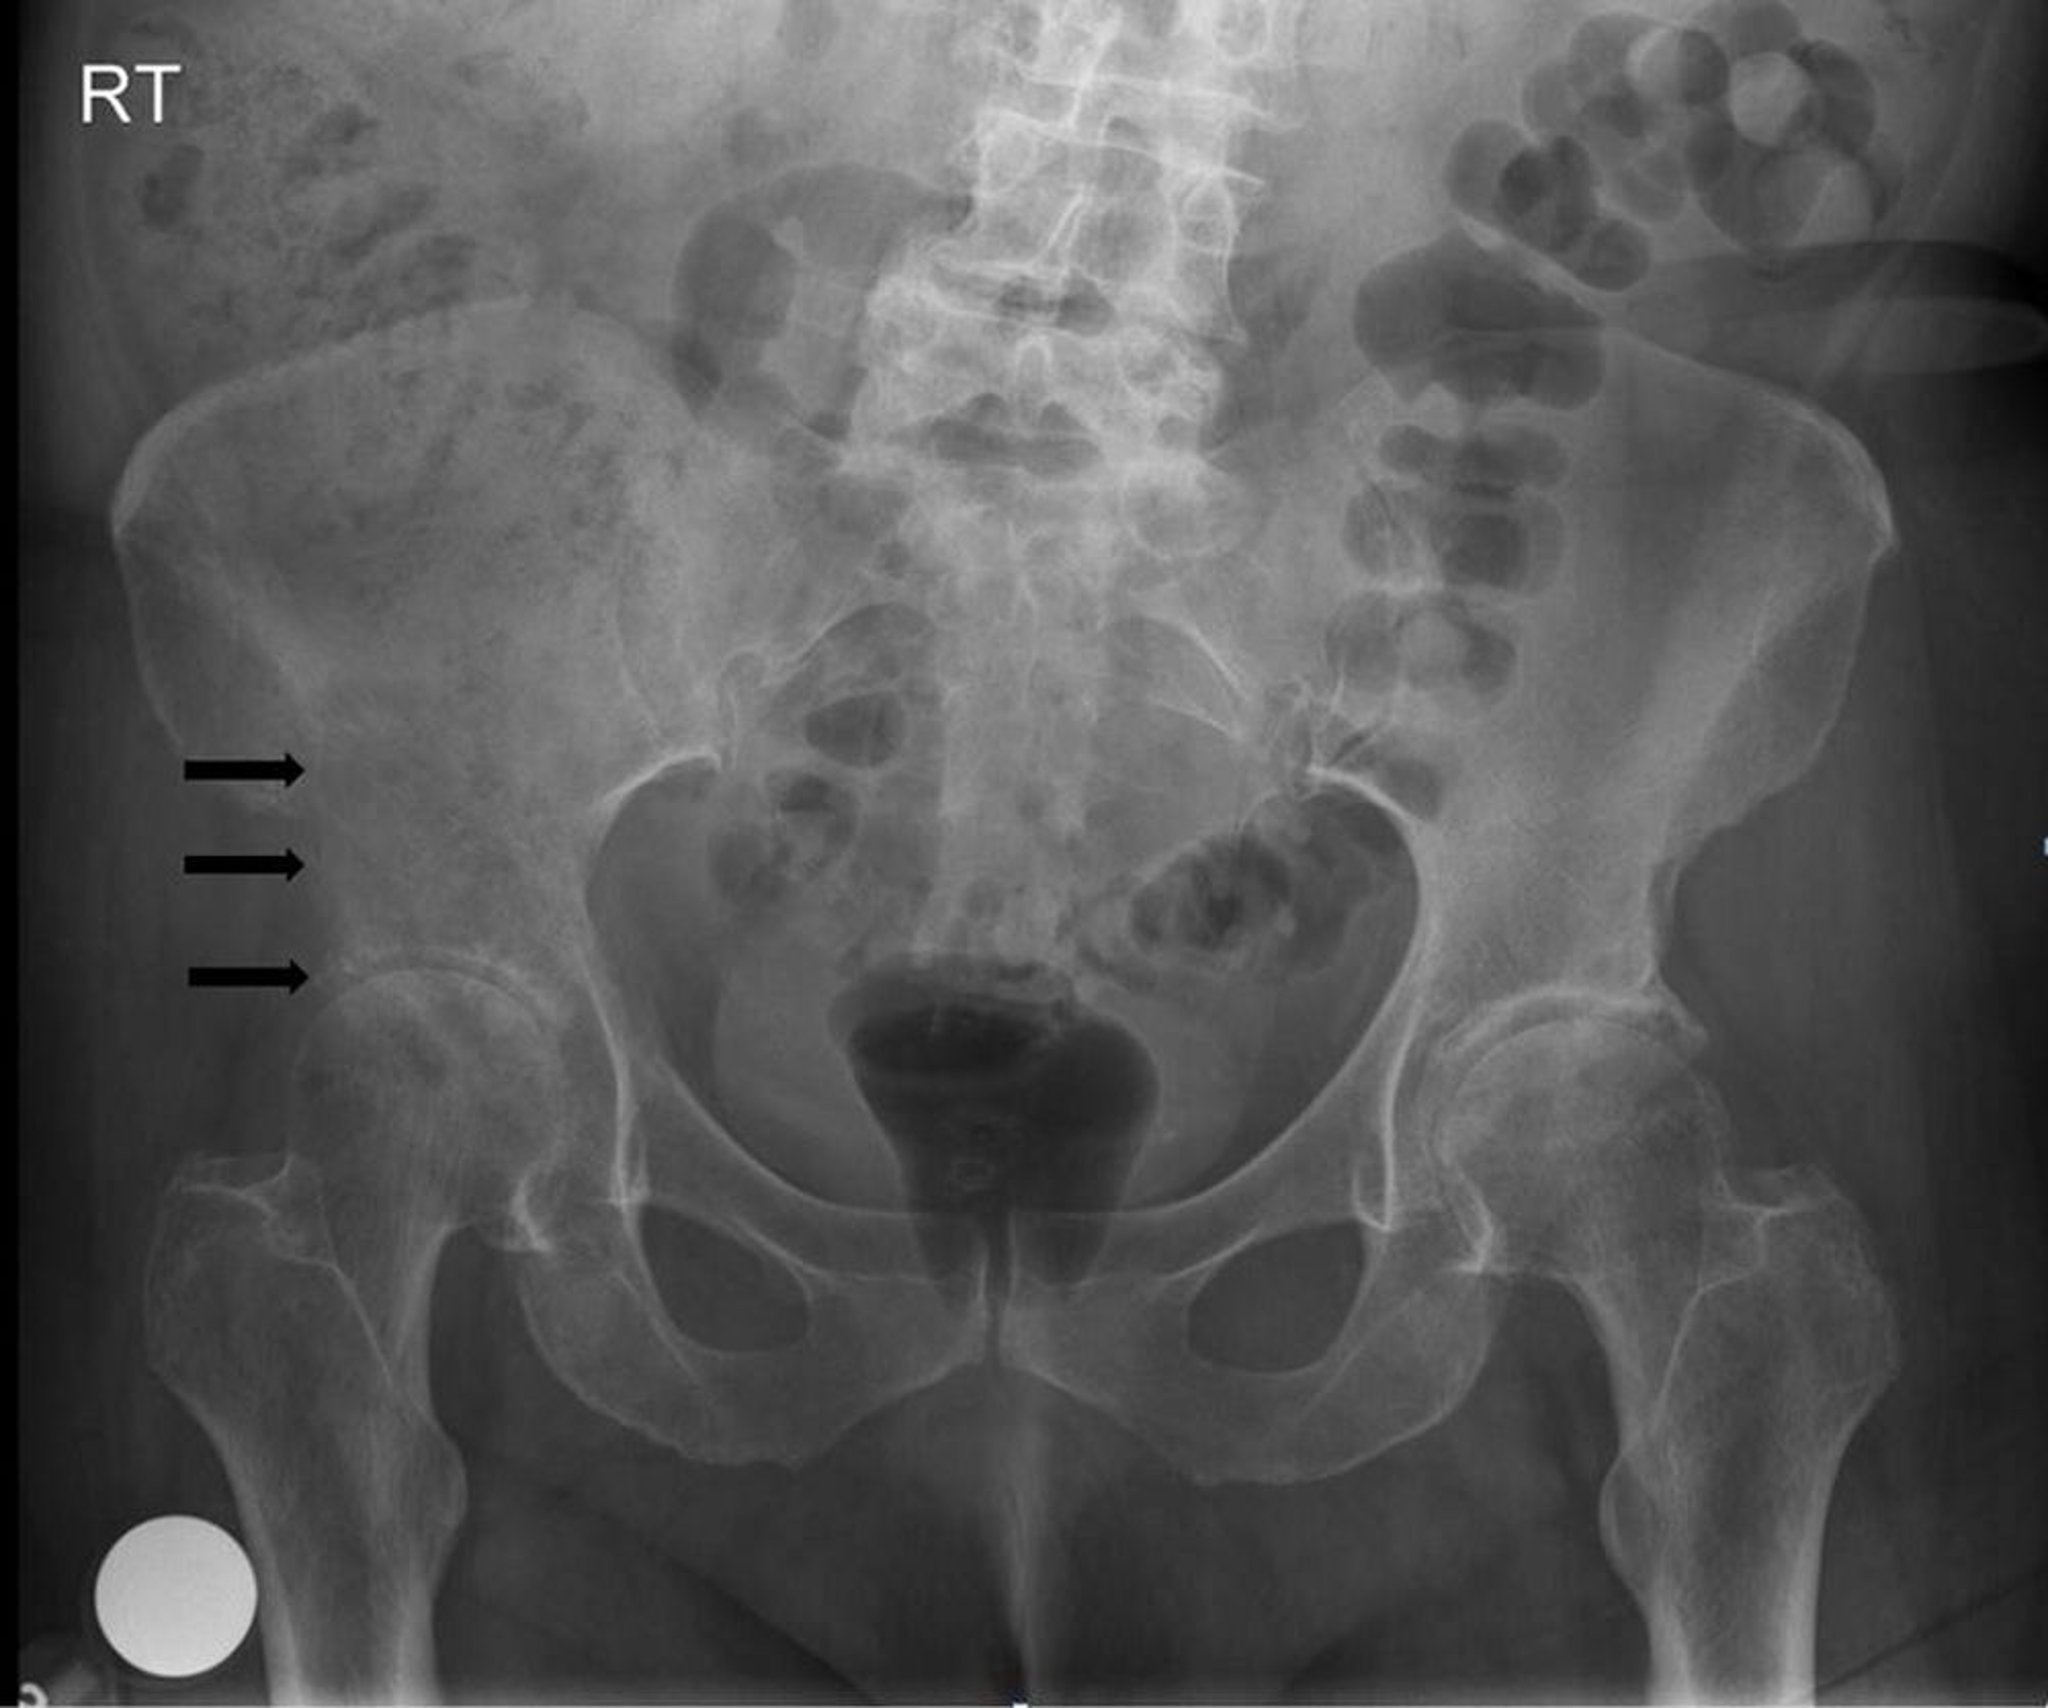

На данной рентгенограмме таза видно литическое, деструктивное поражение в области и выше правой вертлужной впадины (стрелки), что соответствует метастазу.

Image courtesy of Michael J. Joyce, MD, and Hakan Ilaslan, MD.